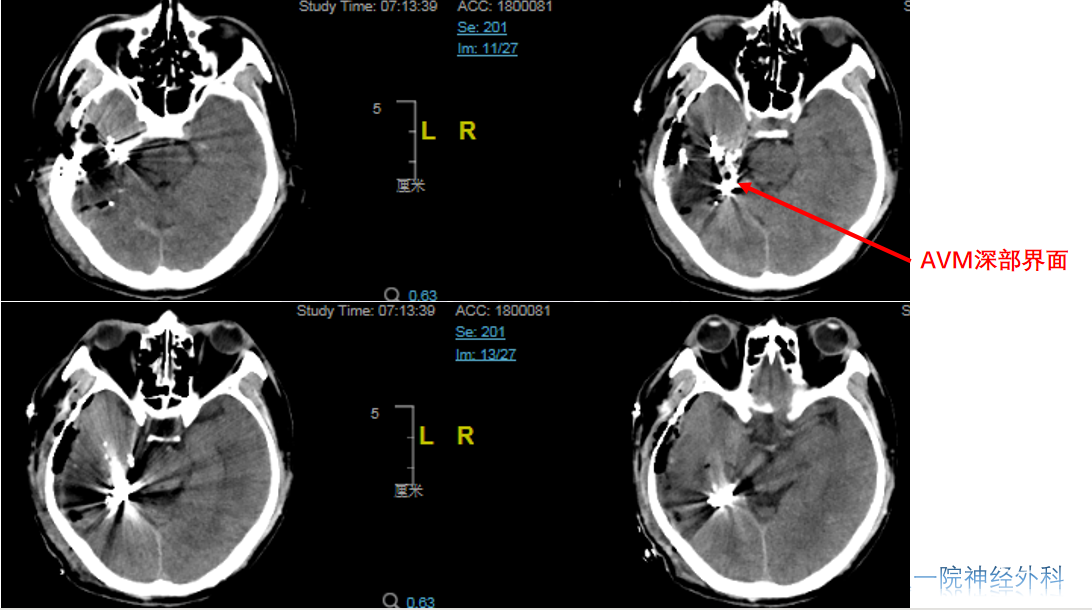

术前CT

栓塞术后CT

术后CT(术后第一天)